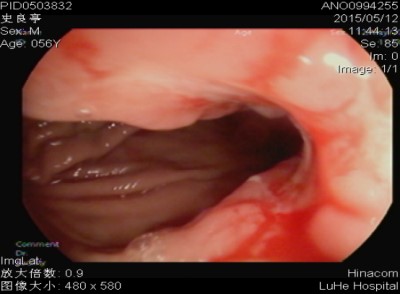

二、胃癌

胃癌病因目前尚不十分清楚。就目前研究资料得知,胃癌的发生与下列因素有关:(1)饮食与生活习惯:咸菜、腌肉、熏制食物为主要副食者,胃癌发病率显著增高。副食品中以蛋白质、新鲜蔬菜、水果摄入量多,则胃癌发生率就明显降低。(2)环境因素:流行病学调查发现,土壤及饮水中缺乏微量元素(如铜、锰、锌、硒、镁)的地区,胃癌发病率就增高。(3)免疫因素:凡免疫功能低下者,胃癌发病相对增高,(4)遗传因素:多数回顾性调查资料认为,胃癌有明显的家族聚集倾向。一般认为,胃癌病人亲属的胃癌发病率比对照组高4倍。(5)感染因素:幽门螺杆菌感染的高危人群患胃癌的危险性较低感染者高6倍。(6)其他因素:许多疾病被认为与胃癌的发生有关,如慢性萎缩性胃炎、慢性胃溃疡、胃息肉等。

胃癌的早期信号:(1)年龄40岁以上,以往无胃病史,突然食欲减退,饭后饱胀,上腹部隐痛或消瘦(2)以往胃病表现的规律疼痛突然改变,按胃溃疡治疗效果不佳。(3)平时胃酸少,爱吃酸性食物或经确诊为萎缩性胃炎或不典型增生,病史较久,又突然消瘦、贫血、怕吃油腻或消化不良症状加重。(4)年龄40岁以上,消化道出血(呕血或黑便),或连续化验大便隐血阳性持续两周以上。(5)胃溃疡经正规治疗两个月以上不愈者。(6)进行性消瘦及贫血者。